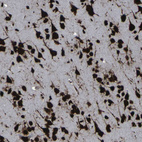

Immunohistochemical staining of human endometrium shows moderate to strong nuclear positivity in glandular cells.